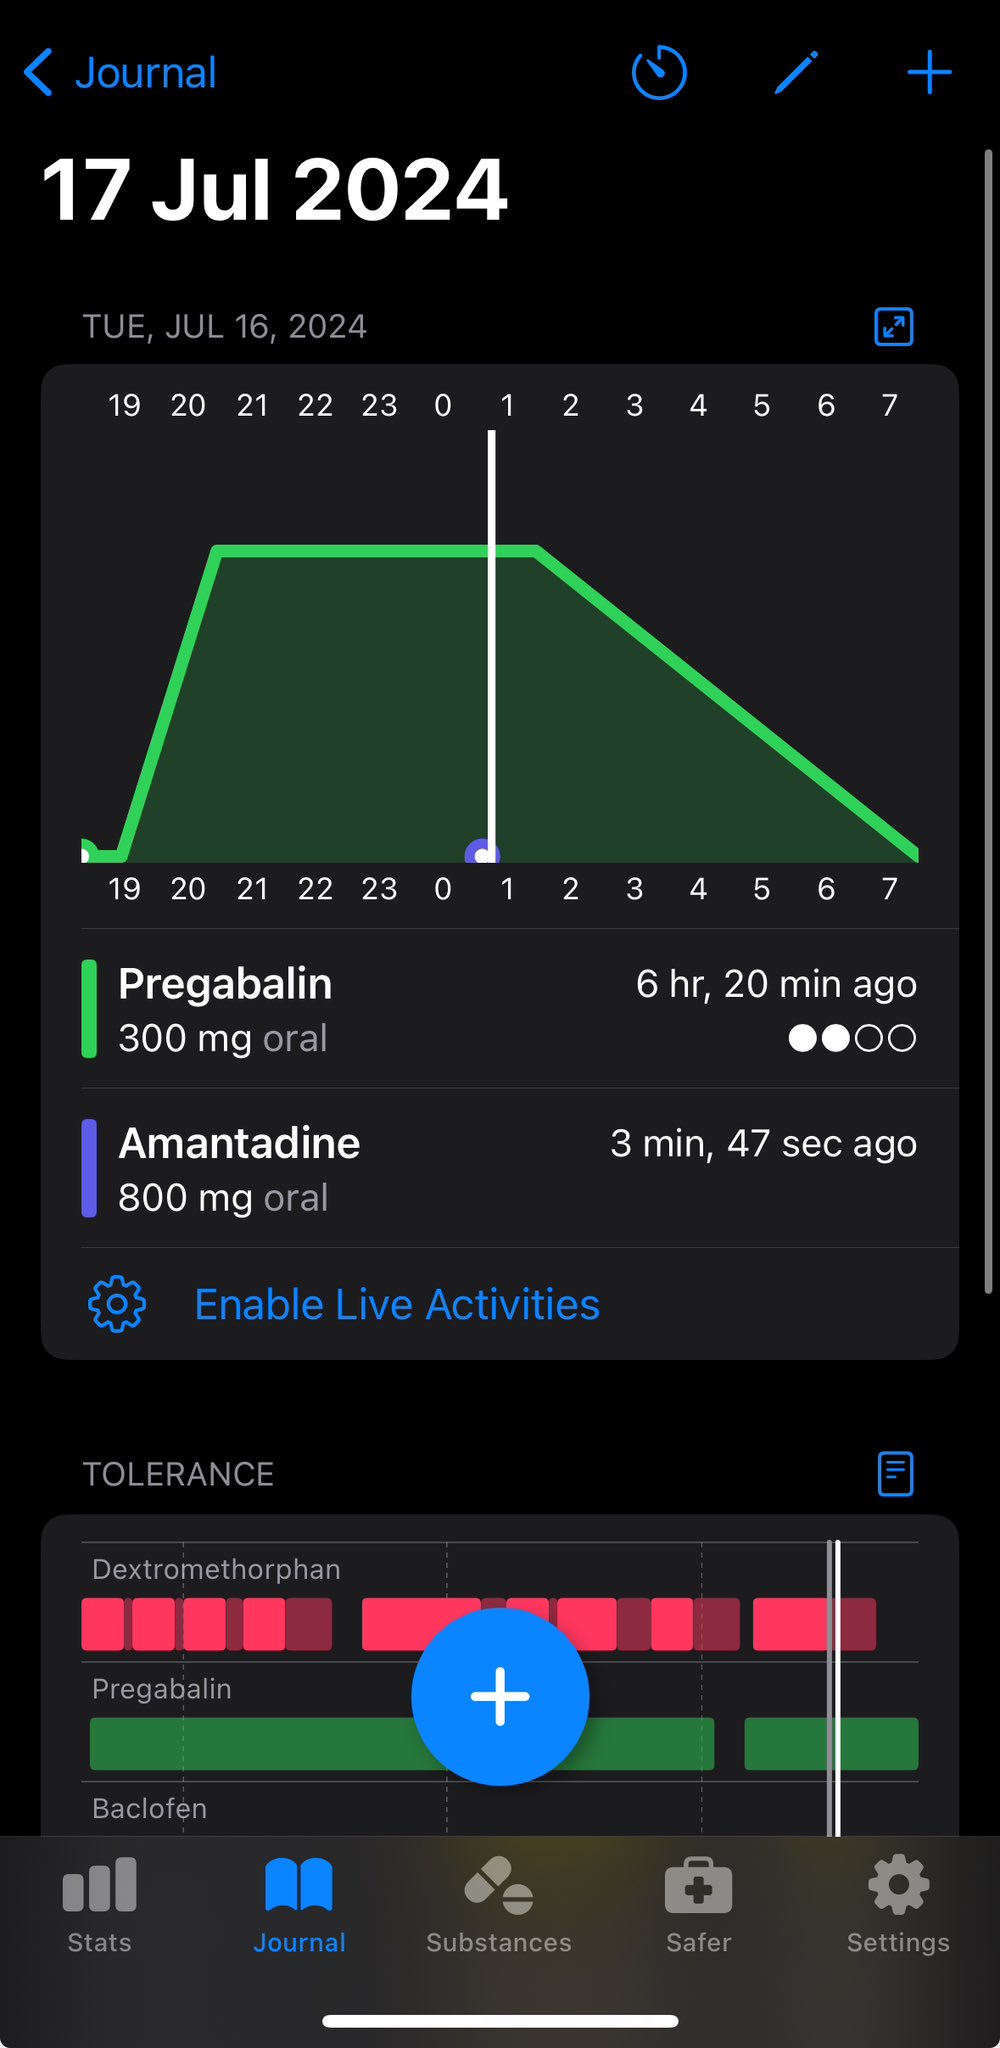

甚至在第二天有余晖的感觉,虽然发生了很多破事但没怎么影响心情*抗焦虑&镇静

运动协调性稍差,表现为走路和站立时平衡不好

此剂量下对睡眠的改善作用,增加了慢波睡眠且没有影响rem,精力恢复+

FDA数据,在临床剂量下(75-600mg)普瑞巴林的依赖性低于bzd,并相比之下它产生的认知和精神运动障碍较轻 https://t.co/TJ7ZOQ7pbC

今天起来特别晕,完全不知道是怎么回事,以为是昨天测试物质的副作用我在想这么恐怖,然后怀疑今天是不是丁螺环酮吃了两次,直到我去看用药记录。。

好家伙唑吡坦又骗我吃药了还顺带上了个失忆状态,这下子知道是谁干的了。吃auv之后dxm清除得特别慢...让我感觉要从此告别了的程度,加上我基因检测本来cyp2d6就是中速代谢,这个尾巴就被拖的特别长